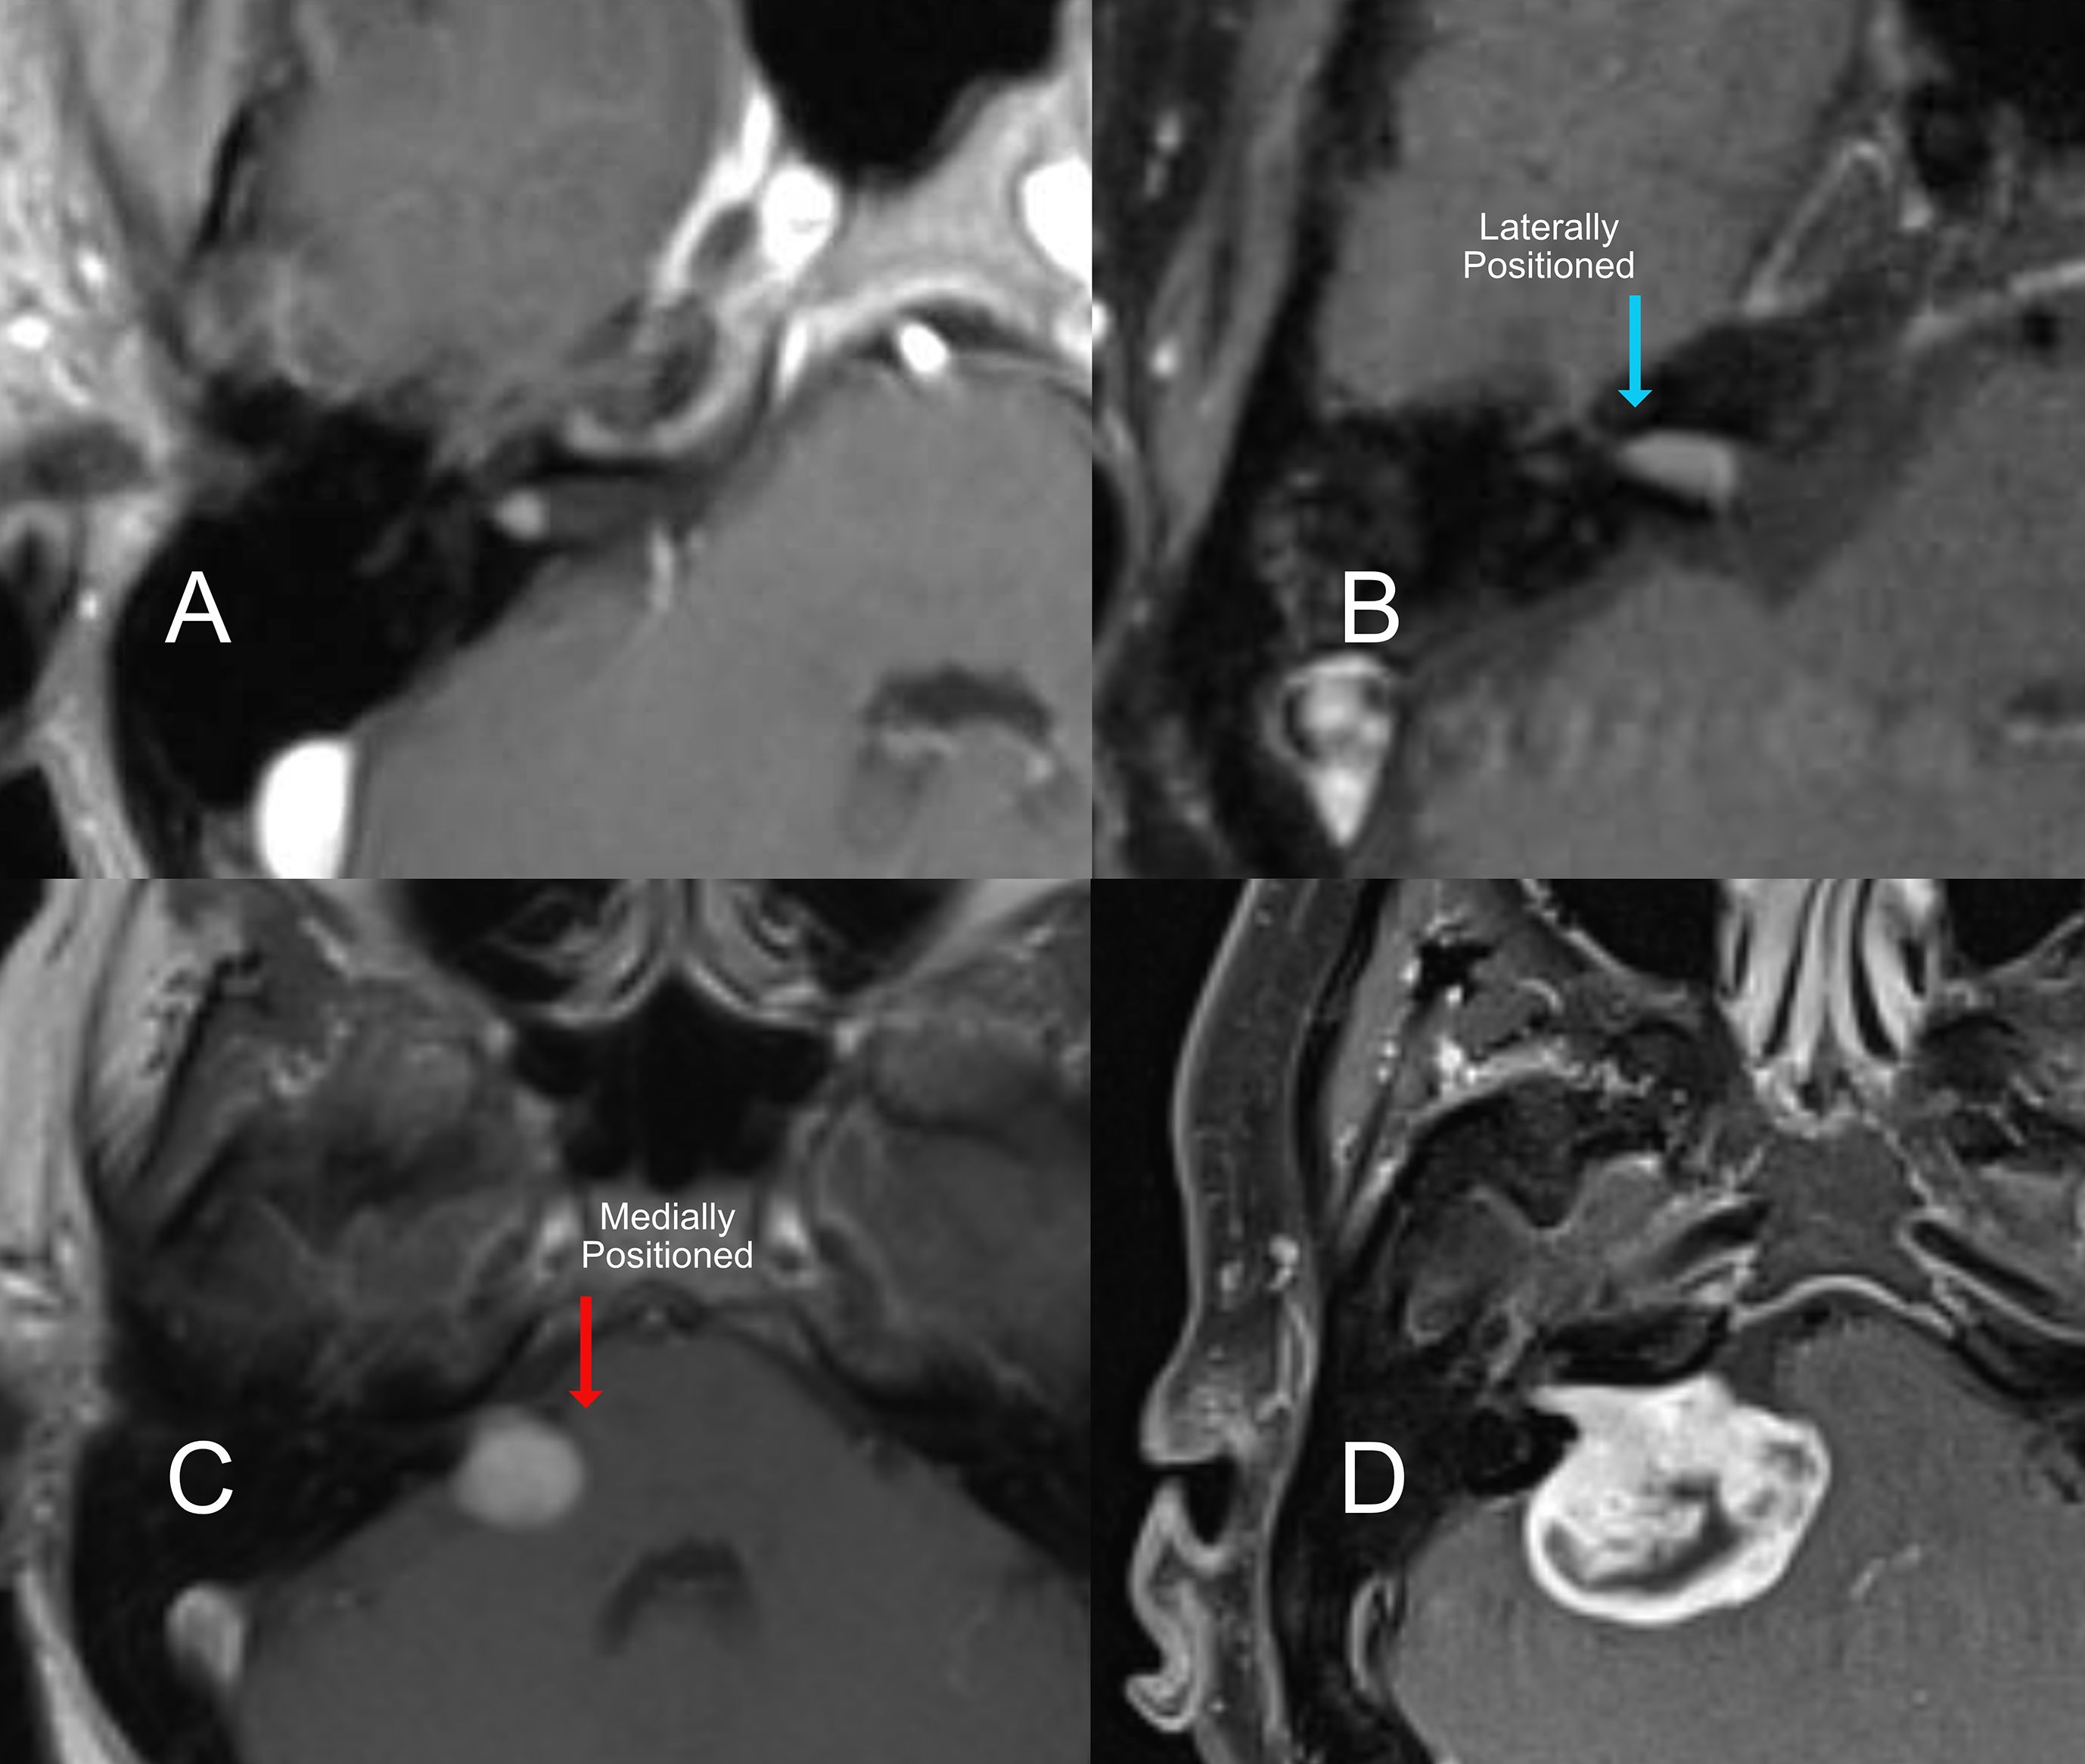

Introduction: Acoustic neuroma (AN) is a benign tumor of the vestibulocochlear nerve, with increasing detection due to improved imaging. Treatment decisions are complex, requiring an individualized approach based on tumor size, location, growth rate, and patient-specific factors such as hearing and vestibular function. Results: Treatment options include observation, microsurgery, and stereotactic radiosurgery. Hearing preservation is prioritized in select cases using middle cranial fossa or retrosigmoid approaches, while translabyrinthine surgery is preferred for larger tumors or disabling dizziness. Stereotactic radiosurgery offers a non-invasive alternative but has variable long-term hearing outcomes and potential tumor regrowth. Vestibular rehabilitation is essential post-treatment, particularly after surgical resection. Discussion: Decision-making depends on patient age, tumor progression, and symptom severity. Younger patients with small tumors may benefit from early intervention to preserve hearing, while older patients with severe imbalance achieve better quality-of-life outcomes with surgery. Stereotactic radiosurgery remains an option for patients unable to undergo surgery, though its long-term efficacy and side effects require careful consideration. A multidisciplinary approach is essential to optimize treatment outcomes. Summary: AN management must be tailored to individual patient profiles. This review integrates current literature and expert clinical experience to guide otolaryngologists, neurologists, and oncologists in treatment planning. Future research should refine treatment algorithms and improve functional outcomes.